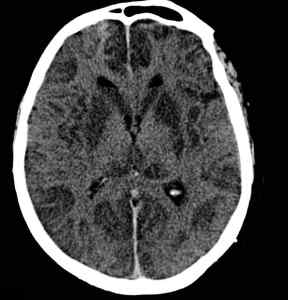

A brain CT scan showing signs of

hypoxic tissue damage.